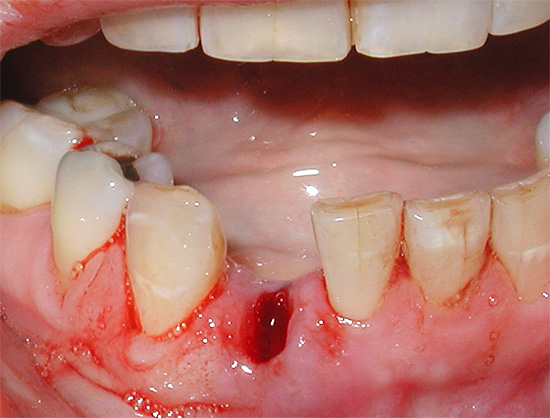

Com um dente traumaticamente rasgado (quando os tecidos circundantes são esmagados e rasgados), a cicatrização das gengivas se estende por um longo tempo, porque após a remoção ocorre uma laceração, cujas bordas estão frequentemente muito afastadas e as seções dos alvéolos (osso) e da lacuna do septo inter-radicular, não cobertas pela margem gengival. Quando a inflamação do tecido ocorre dentro e ao redor do poço, as bordas da ferida não se juntam por muito tempo e a epitelização não termina após 2 semanas, mas pode levar de 30 a 50 dias.

Somente após 4-5 meses, a formação de tecido ósseo jovem é concluída e a versão final da "cobertura" gengival é formada sobre o orifício.